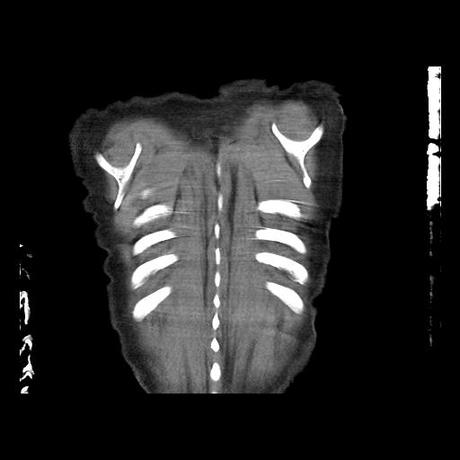

Se realiza volumen de tórax en fase simple, desde los opérculos torácicos hasta los hemidiafragmas, observándose:

Estructuras óseas sin evidencia de lesiones líticas, blásticas ni trazos de fractura. A nivel de cuerpo vertebral de T10 se observa nódulo de Schmorl que distorsiona el borde superior del cuerpo vertebral.

El parénquima pulmonar con areas parcheadas difusas en vidrio despulido combinadas con otras areas hipodensas de baja atenuación debidas a atrapamiento aéreo y engrosamiento intersticial y zonas de fibrosis de predominio en lóbulos medios e inferiores de ambos pulmones.

En los cortes valorados de abdomen hígado, bazo y páncreas sin evidencia de alteraciones, glándula suprarrenal izquierda con imagen ovalada, bordes definidos, homogénea, mide 11 mm en probable relacion a adenoma.

- LOS HALLAZGOS PUEDEN ESTAR EN RELACIÓN A NEUMOPATIA INTERSTICIAL PROBABLE ETIOLOGIA HIPERSENSITIVA VS AUTOINMUNE/BACTERIANA/FUNGICA.